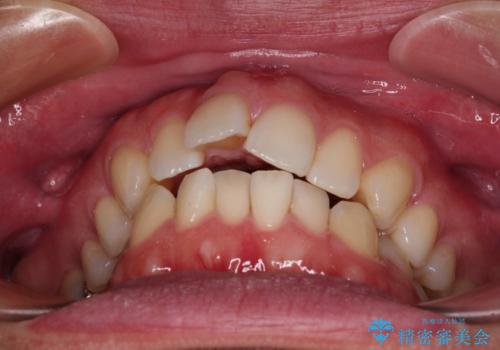

- 口元の突出感と下の前歯のがたつきを主訴として来院された患者様です。

口元の突出感と叢生改善のため上下左右の第一小臼歯4本を抜歯し、ワイヤー装置にて矯正治療を行うこととしました。

なるべく目立たない装置が希望だったため、審美装置で治療を行いました。